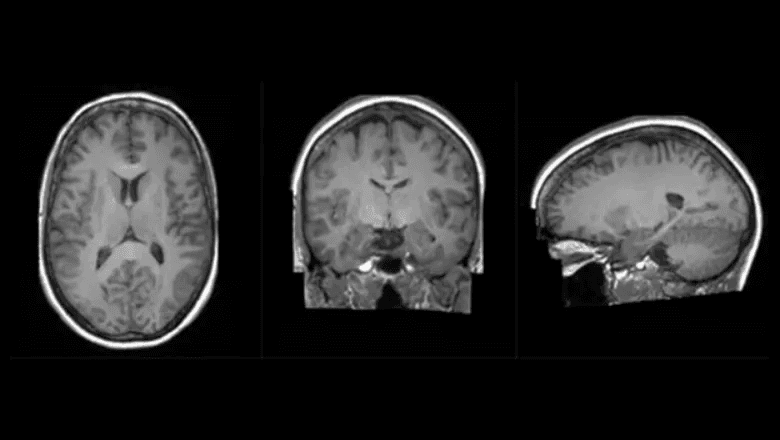

Synthetic Brain Scan

The Synthetic Brain Project is focused on building deep learning models that can create artificial 3D MRI images of human brains. These models can help scientists understand what a human brain looks like across a variety of ages, genders, and diseases. The AI models were developed by King’s College London and NVIDIA data scientists and engineers as part of The London Medical Imaging & AI Centre for Value Based Healthcare research and a Wellcome Flagship Programme (in collaboration with University College London).

The aim of developing the AI models is to help diagnose neurological diseases based on brain MRI scans, but it may also be used to predict diseases that a brain may develop over time and enable preventative treatment. The use of synthetic data has the additional benefit that it can ensure patient privacy since the images were generated and it will open up research to the broader UK healthcare community. Without Cambridge-1, the AI models would have taken months versus weeks to train and the resulting image quality would not have been as clear. King’s and NVIDIA researchers used Cambridge-1 to scale the models to the necessary size using multiple GPUs, and then applied a process known as hyperparameter tuning, which dramatically improved the accuracy of the models.

The 3 dimensional nature of the data required unparalleled model sizes that were only made possible by the multi-GPU and multi-node scaling provided by Cambridge-1. Creating these generative brain images that are eerily similar to real life neurological radiology studies (examples here) can be ground-breaking when understanding how the brain forms, how trauma and disease affects it, and how to help it recover. Instead of real patient data, the use of synthetic data can also help mitigate problems with data access and patient privacy.